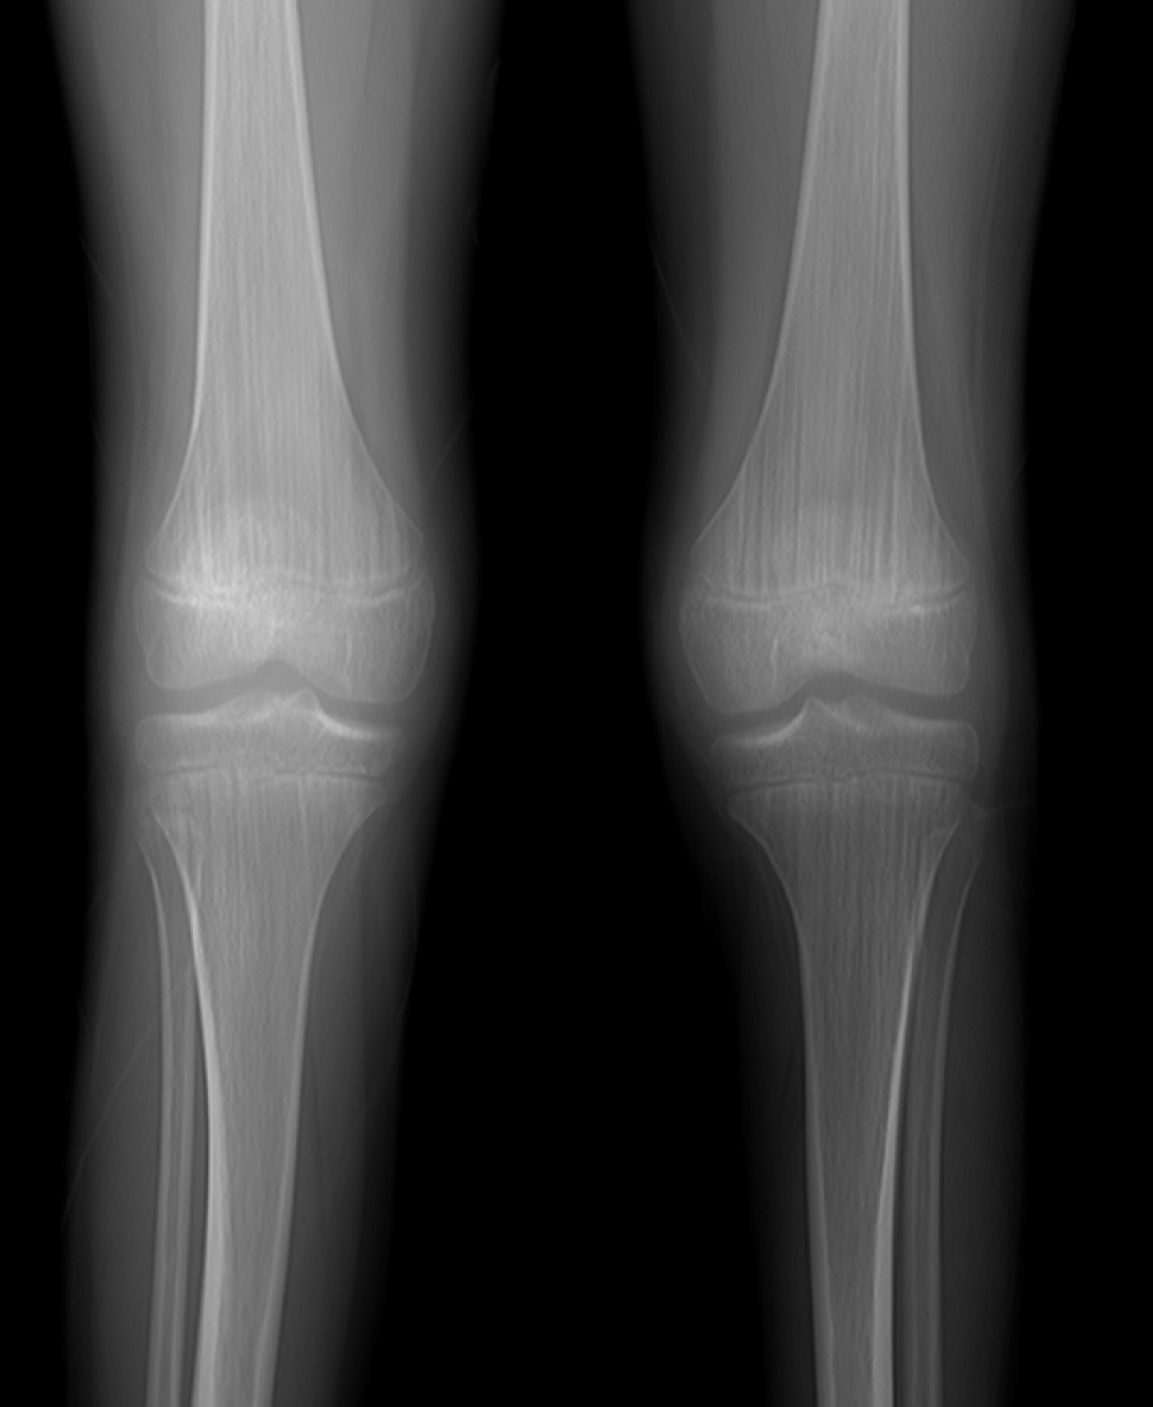

Figure 2

Vertical striations in the metaphyseal regions of the femoral and tibial bones on radiographs.